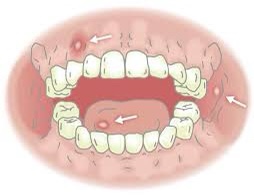

口内炎の種類と原因とは?症状や原因、対処や治し方について知る。

口内炎の原因と種類とは?できやすい場所・症状・早く治す方法や予防法を解説。

口内炎の種類とは?アフタ性口内炎など5種類の特徴を詳しく解説 チョコラドットコム。

口内炎の種類JR古河駅 徒歩3分の歯医者 佐藤デンタルクリニック。